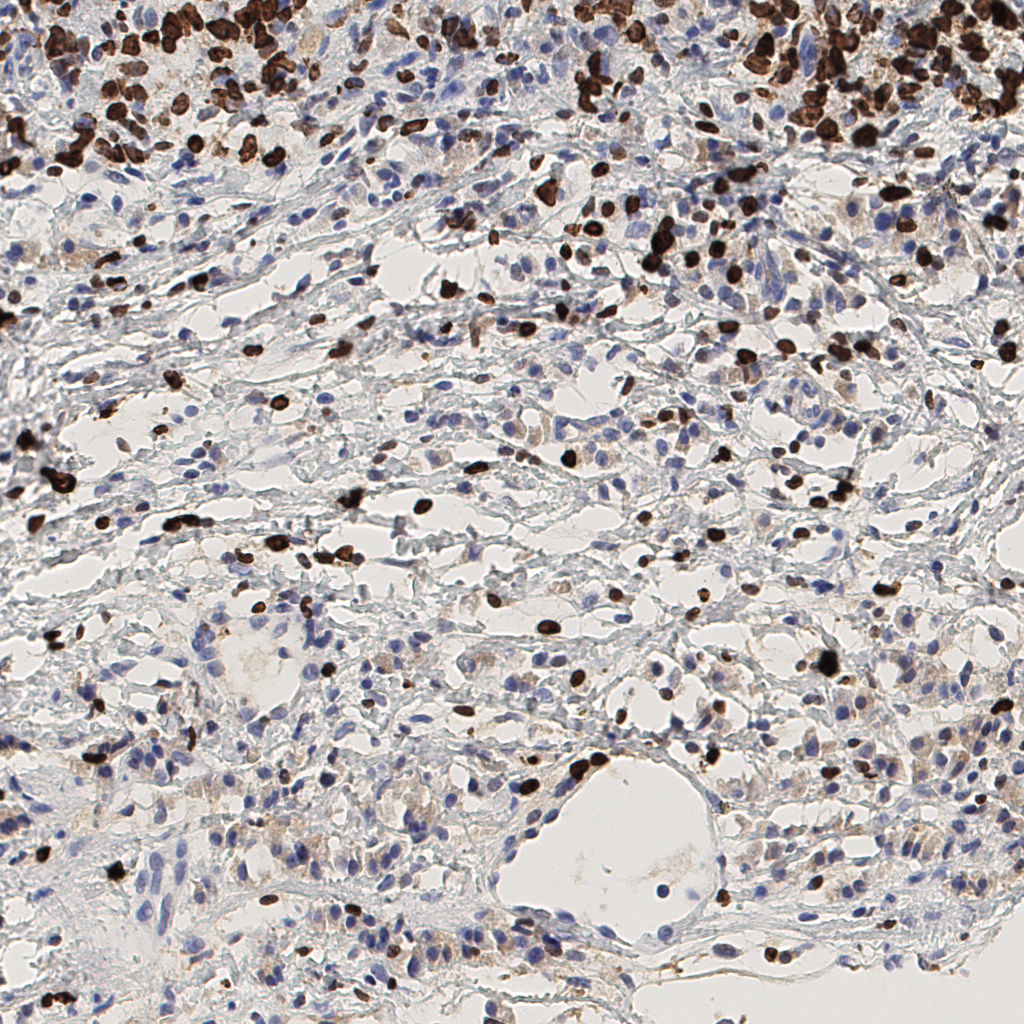

7.85%

Ki67 指数

阴 1104

阳 94

切片统计

总切片

1953

有效

288

已标记

有效率

15%

标记后

标记前